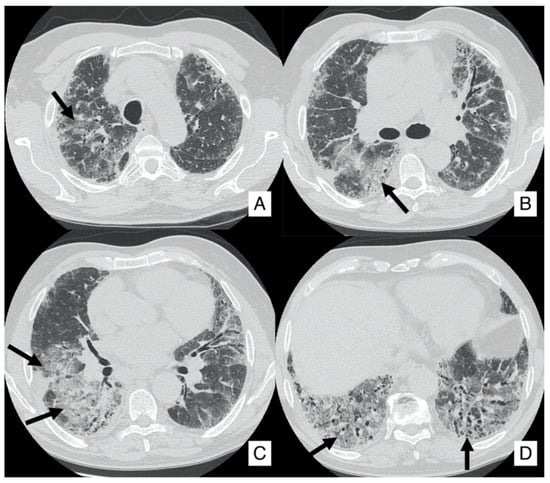

4.1. Lung Cancer

4.2. Acute Exacerbation